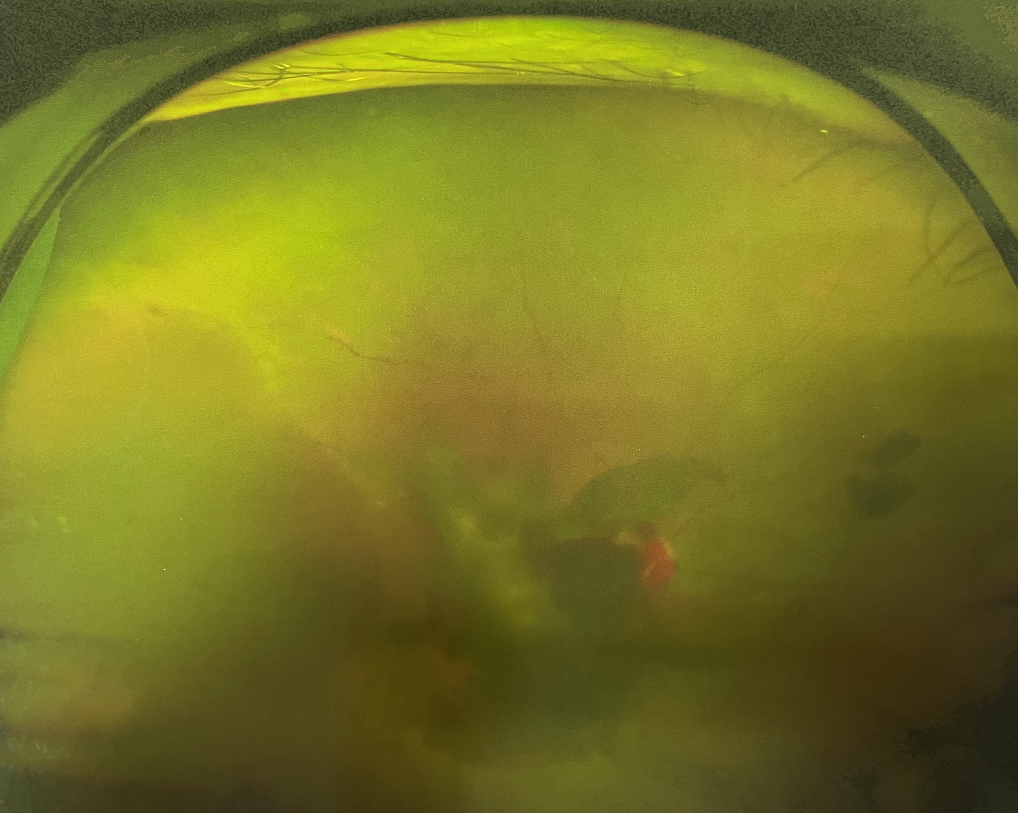

眼底出血多指玻璃體內(nèi),眼睛更深處的視網(wǎng)膜出血。通常情況下,肉眼難以發(fā)現(xiàn)眼底出血,而且發(fā)病初期眼睛也無明顯癥狀,只有借助專業(yè)的眼底檢查儀器才能觀察到異樣。那么眼底出血嚴(yán)重嗎?

眼底出血嚴(yán)重嗎?其中,“三高”患者、高度近視患者和滲出性或濕性老年黃斑變性患者是眼底出血的高發(fā)人群。

醫(yī)生提醒,一旦眼睛出現(xiàn)視力下降、視物變形、視野缺損或眼前有黑影等視覺“異常”的情況,應(yīng)及時到醫(yī)院進(jìn)行眼底檢查,及早發(fā)現(xiàn),及早治療,以免貽誤病情。